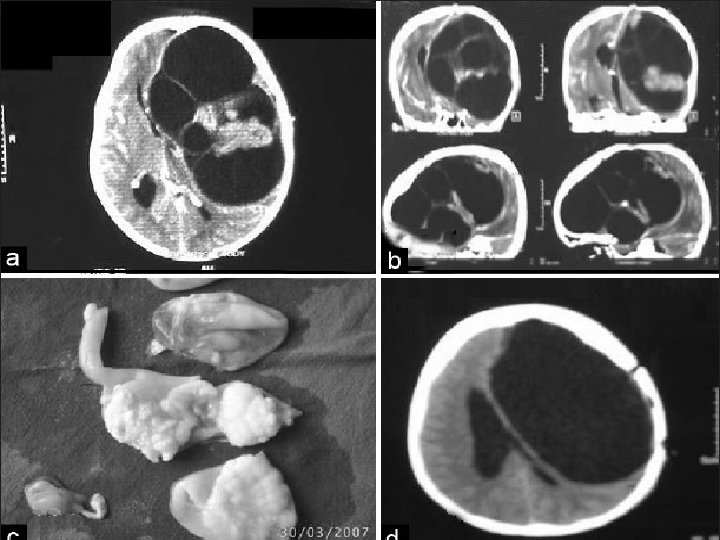

CYSTIC HYDATID DISEASE OF THE BRAIN • Dowling's technique: hydrostatic expulsion of the entire cyst by irrigation of saline solution between the lesion and the surrounding nervous tissue. • The aim of this technique is to remove the cyst without damaging its walls.

accidental intraoperative rupture • 25% of cases. • allergic reaction. • recurrent hydatid disease.

Complications: subdural effusions and intracranial hemorrhages. • some surgeons puncture the cyst, aspirate its contents, irrigate the cyst with a hypertonic saline solution, and then remove the shrunken cyst.

Pathology • E. granulsus cysts are large, spherical, and well demarcated from surrounding tissue. • within the CNS, these cysts may be located in the brain parenchyma, ventricular system, subarachnoid space, epidural space, orbits, and both the epidural and subarachnoid spaces in the spinal canal.

CYSTIC HYDATID DISEASE OF THE SPINE • The surgical approach to patients with spinal hydatid disease usually includes a combination of : • decompressive laminectomy, • removal of cysts. • excision of involved bone. • stabilization of the spine.